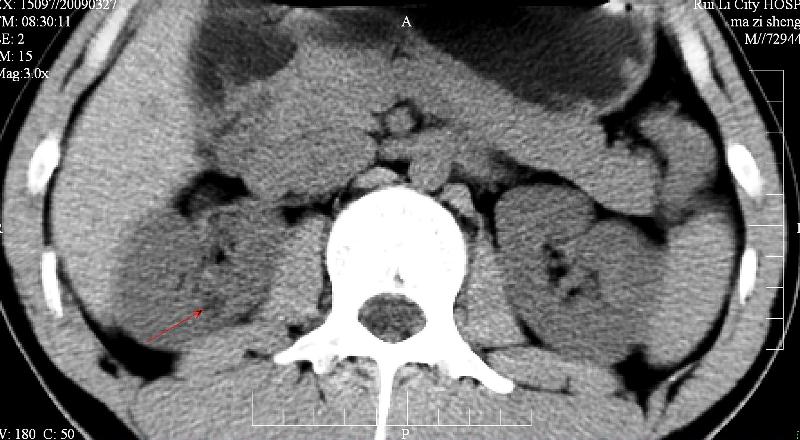

标题: CT19133:M,28岁。 [打印本页]

标题: CT19133:M,28岁。

ct发现左肾小结石而右侧腰部疼痛?右肾是伸入实质的肾盏吗?

增强再看,囊肿可能

建议增强,囊肿可能